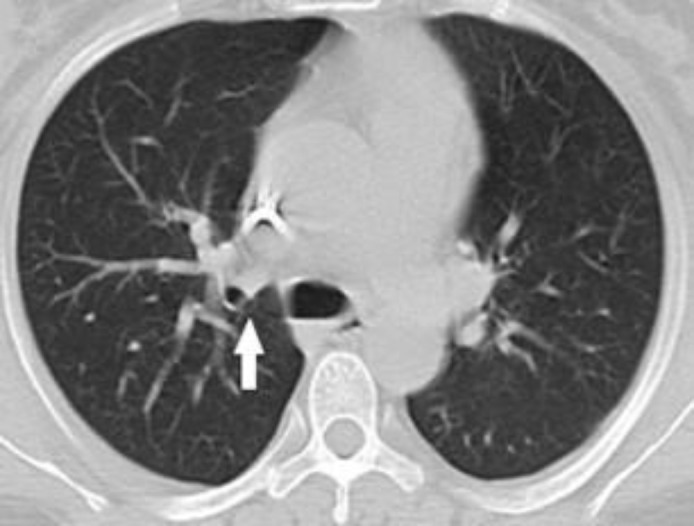

Gastrointestinal sarcoidosis mimicking malignancy: A confusing scenario.